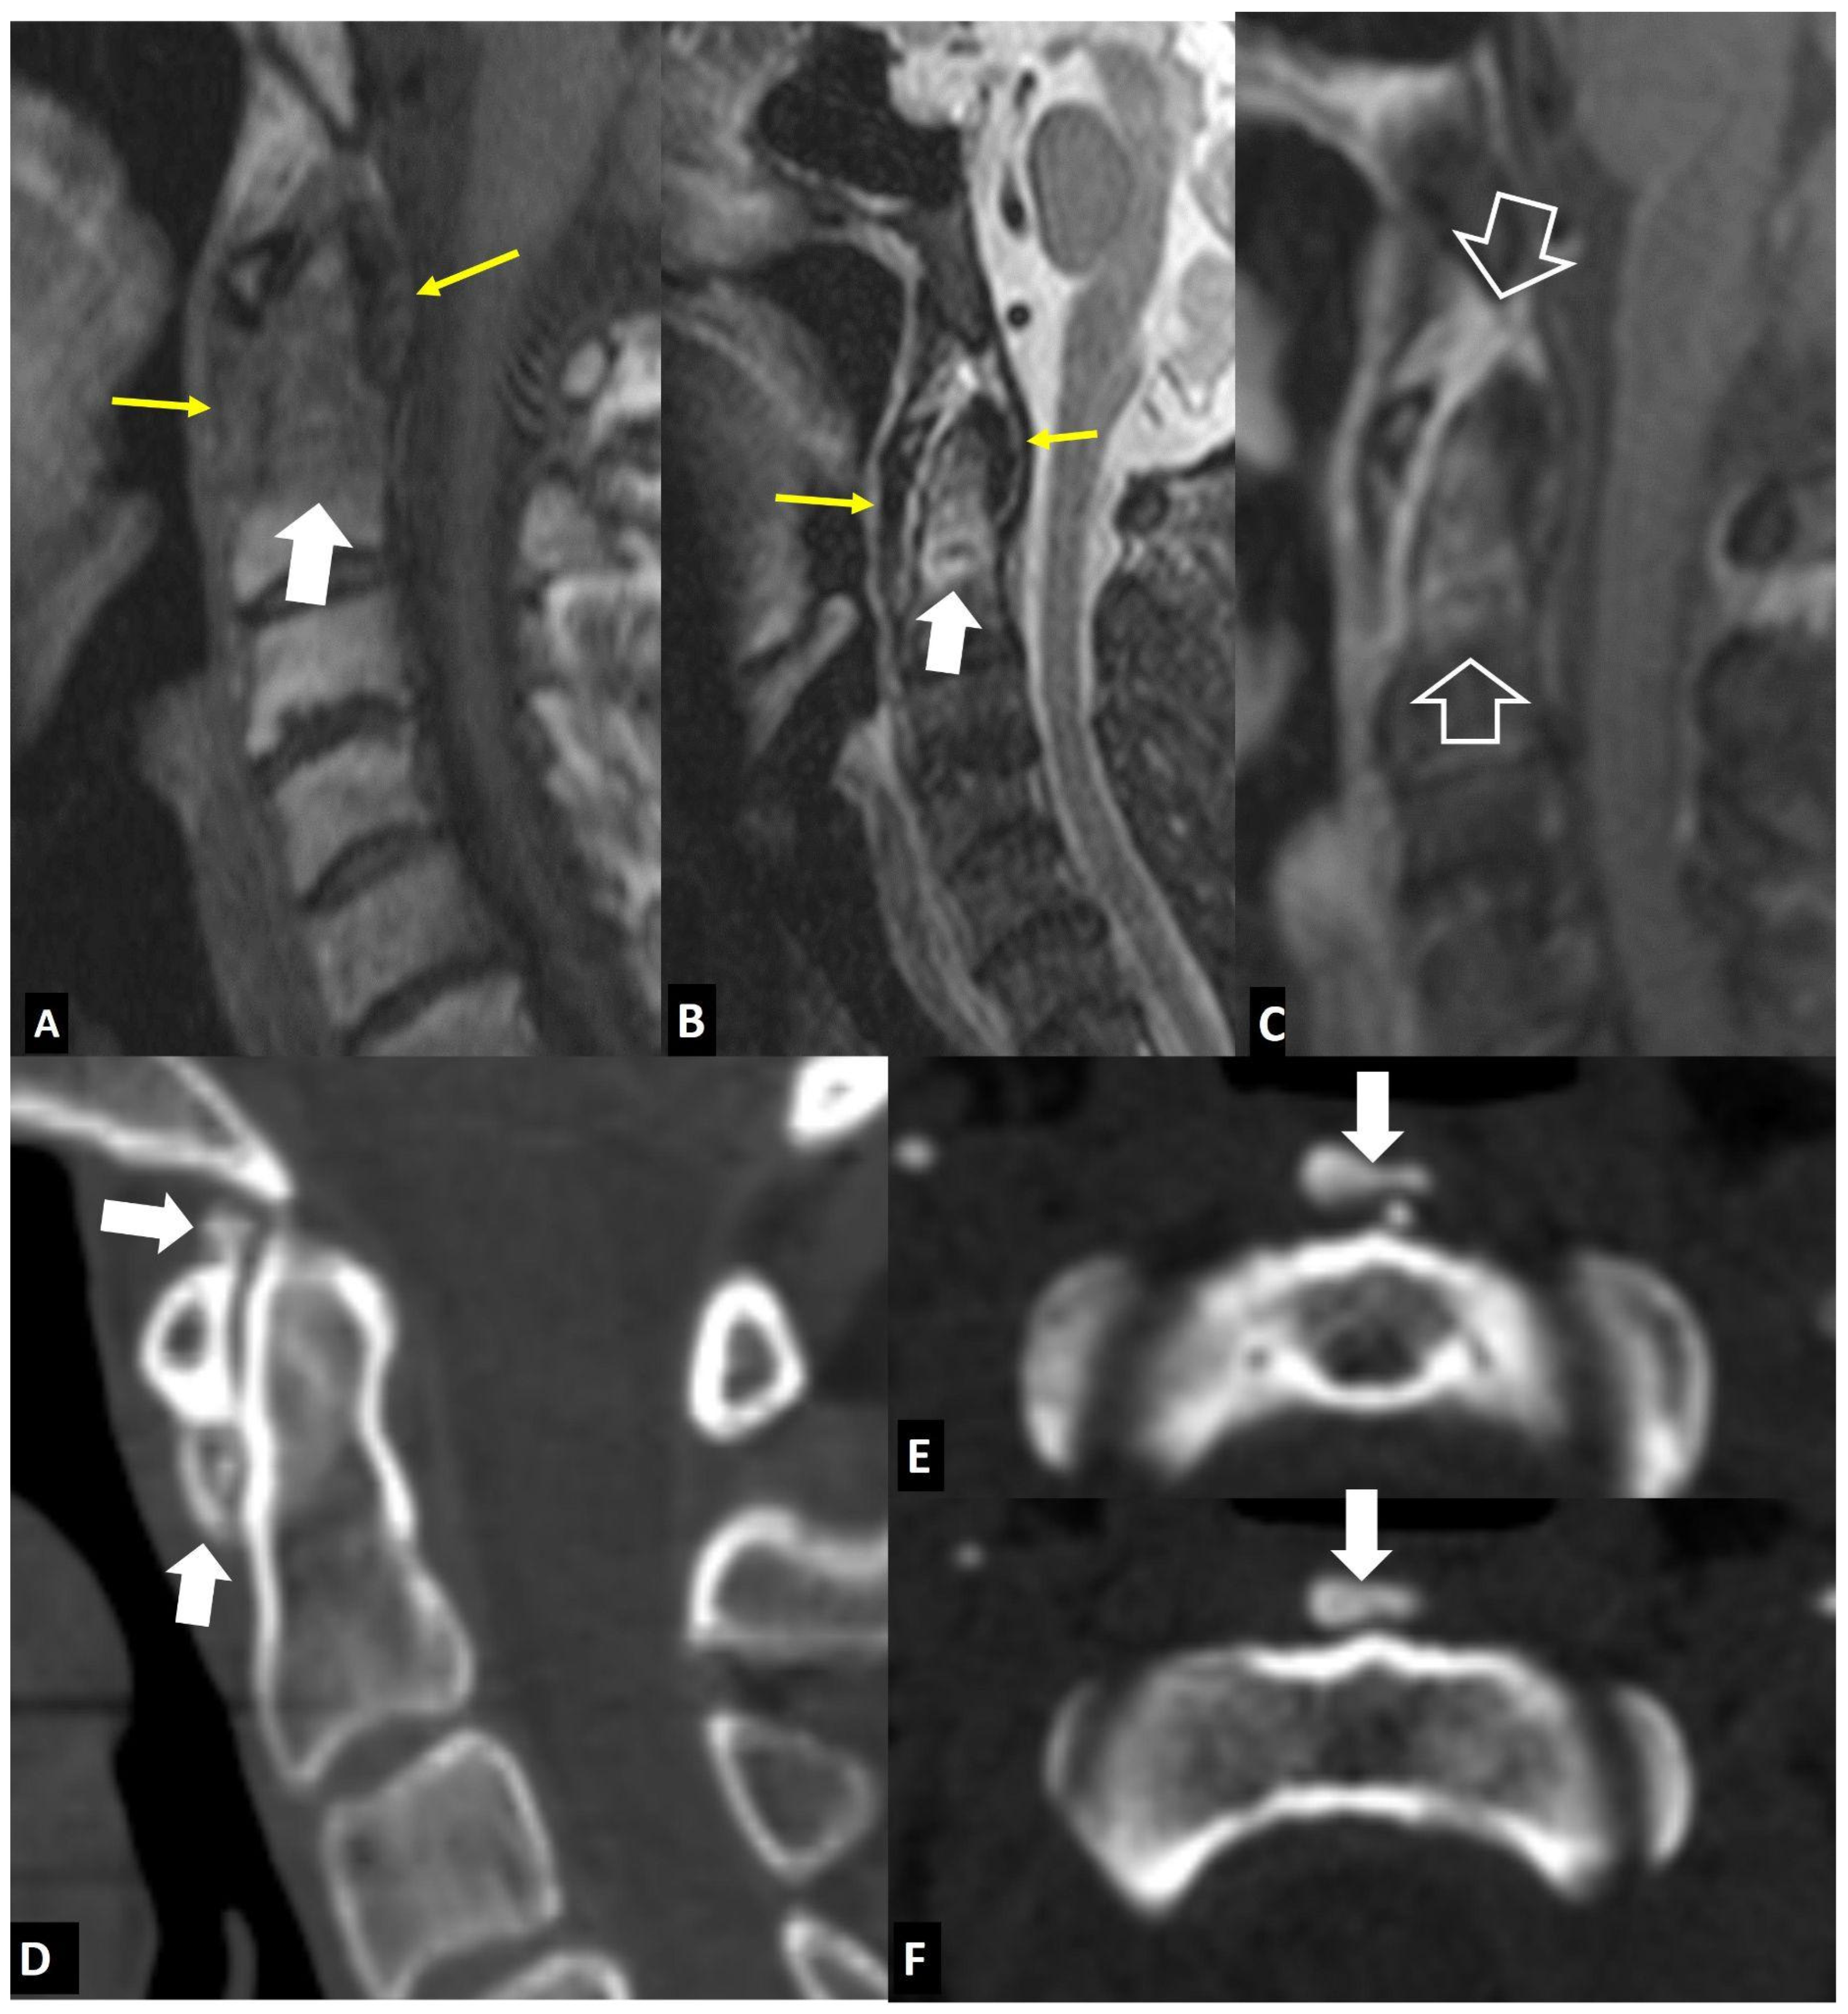

2.1.8. Rheumatoid Arthritis

2.2. Non-Infectious Sacroiliitis